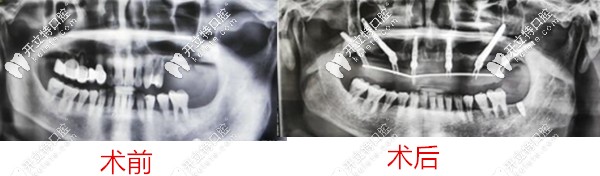

2、弟弟,60歲

種牙前牙齒問題:全口牙松動、多顆缺失,牙槽骨流失;

種植方案:雙側(cè)穿顴穿翼,種植6顆恢復(fù)14顆。